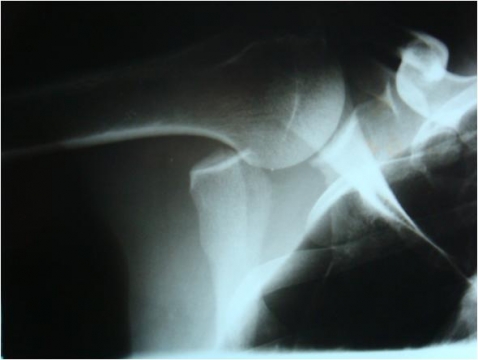

Fratura de escápula

- RX: fratura da escápula

CONDUTA: TRATAMENTO CIRÚRGICO: REDUÇÃO CRUENTA + FIXAÇÃO INTERNA COM PARAFUSO INTERFRAGMENTAR + PLACA DE APOIO